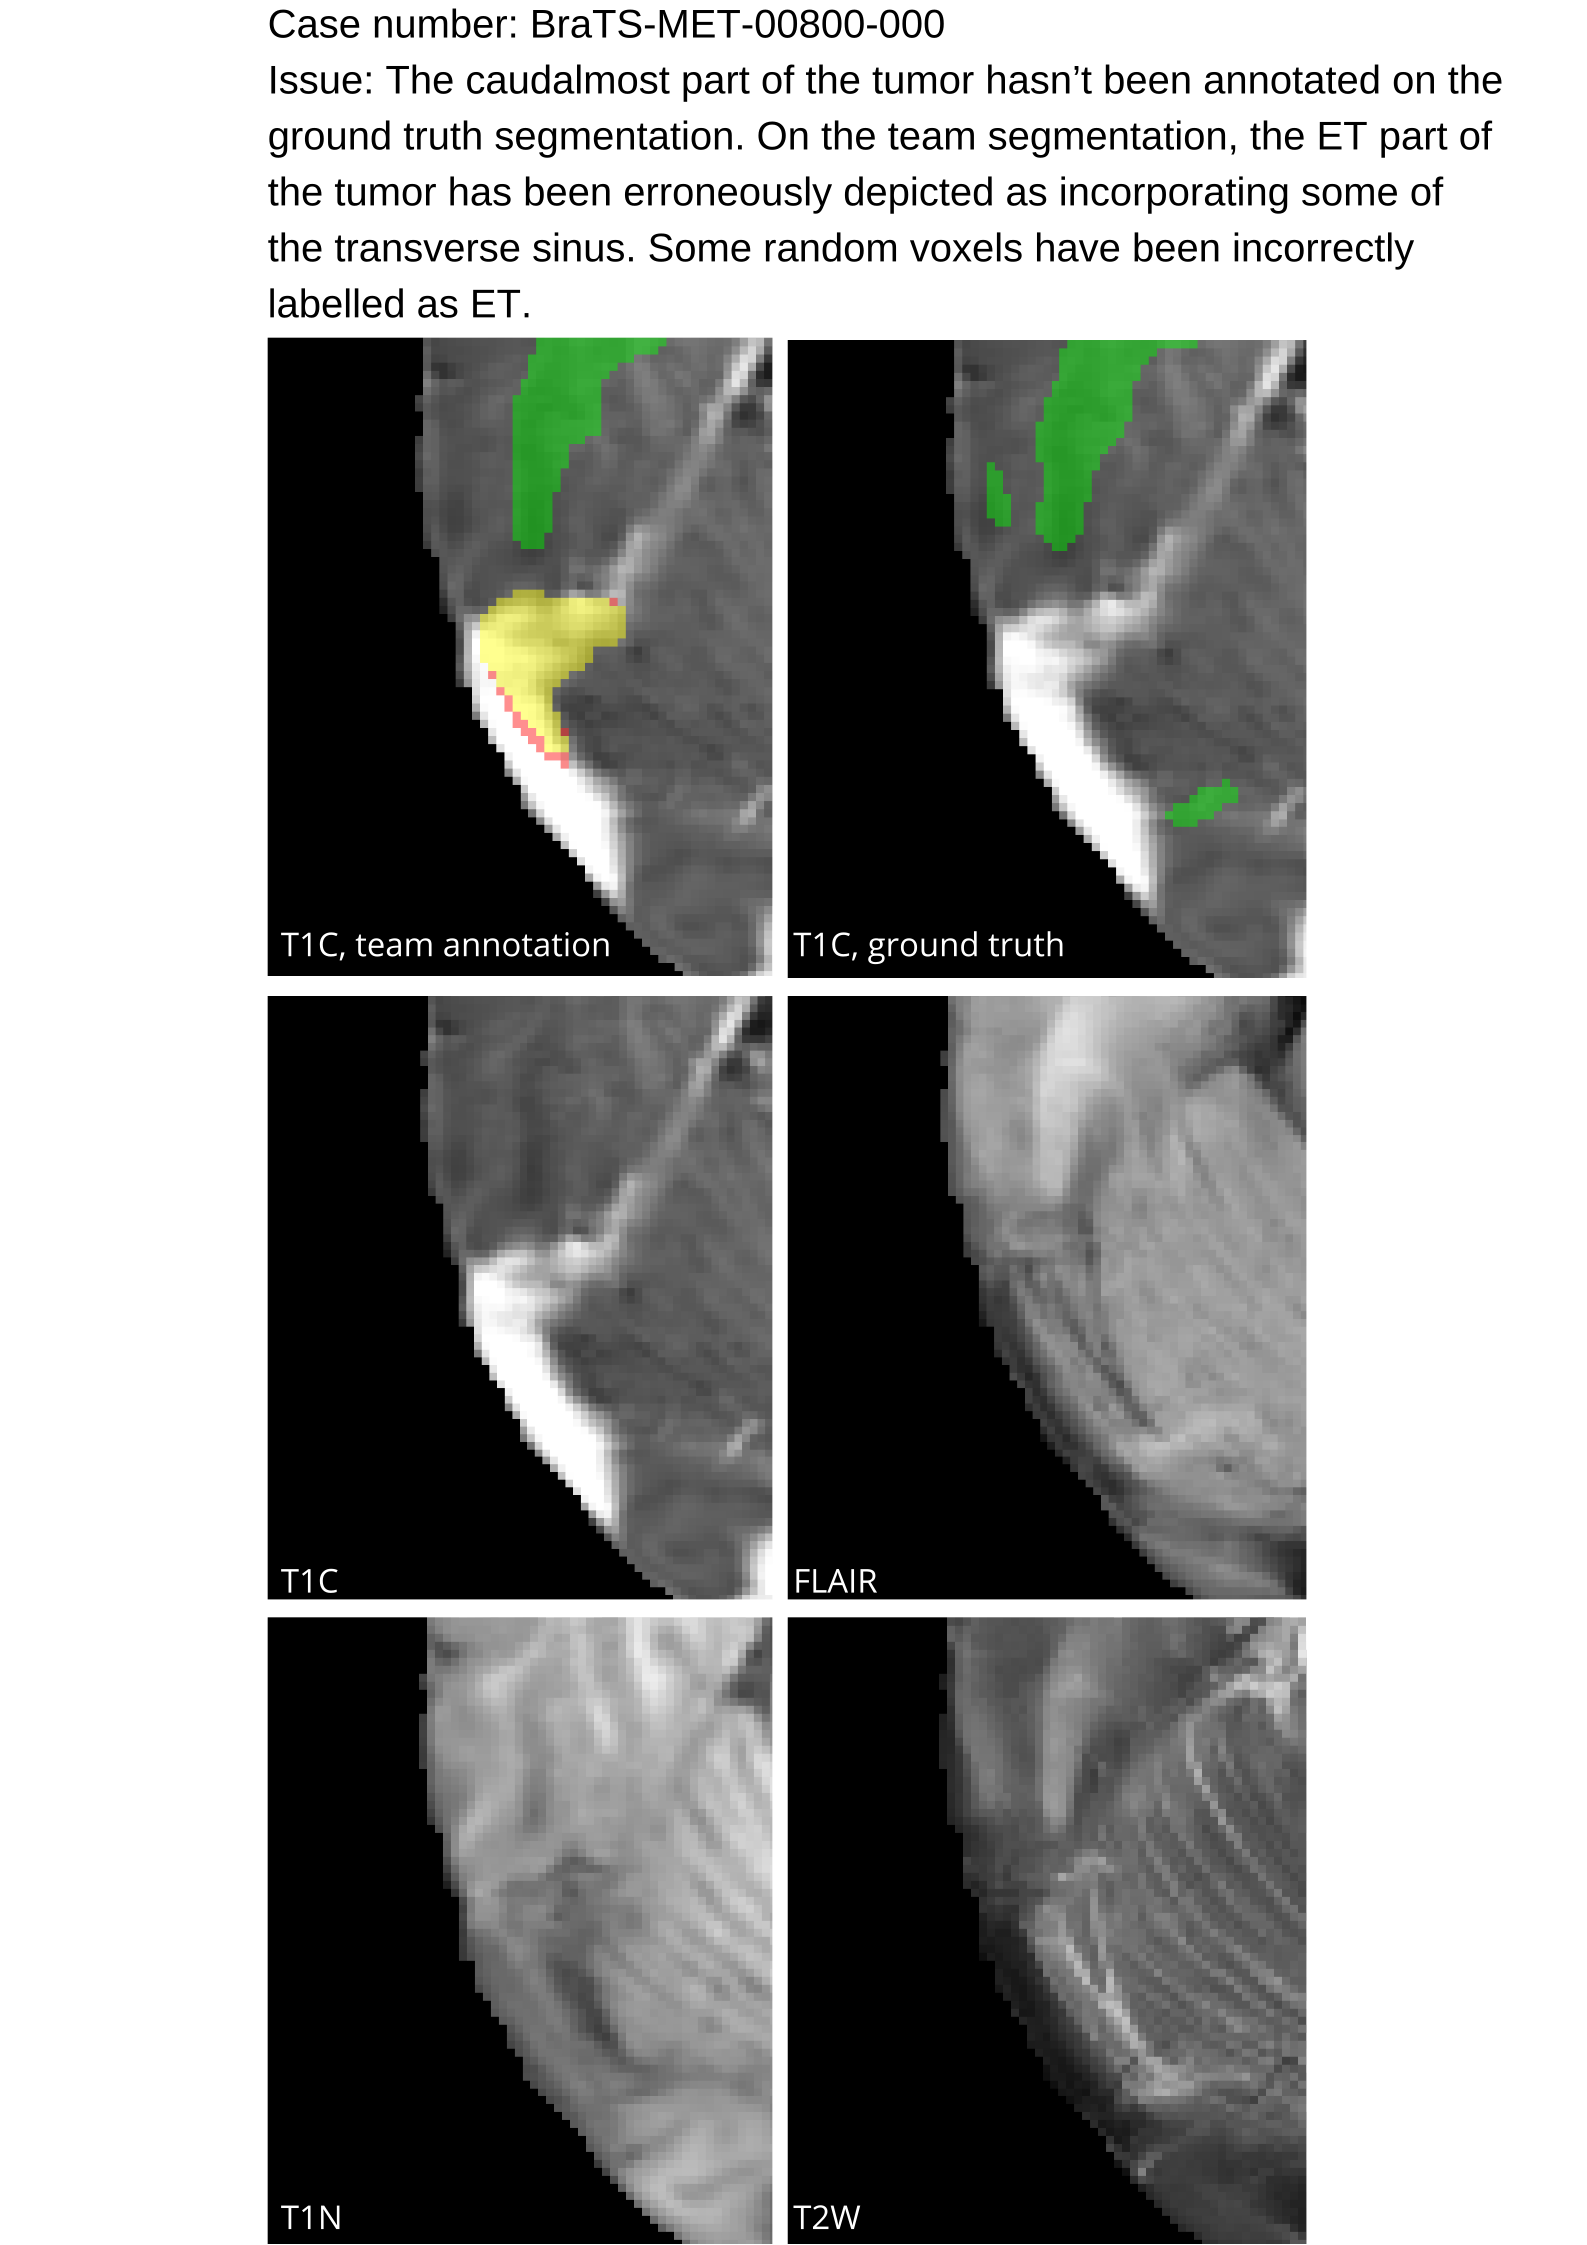

Approvers reviewed the volunteer annotations and either approved the case or returned it to students for re-annotation. Additionally, a QC process was implemented, which included removing all random voxels and any voxels outside the brain mask, ensuring all images had the same parameters (space, orientation, and origin) as the SRI24 atlas, and verifying the presence of all segmentations and segmentation masks are in the folder with original NIfTI images.